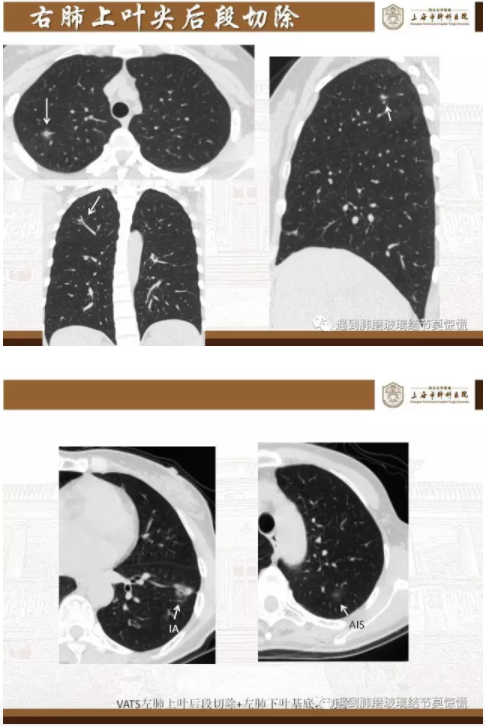

下面就我们的病例分析一下怎么进行肺段切除。

MIA= 微浸润腺癌   IA= 浸润性腺癌   AIS= 原位腺癌   AAH= 不典型腺瘤样增生